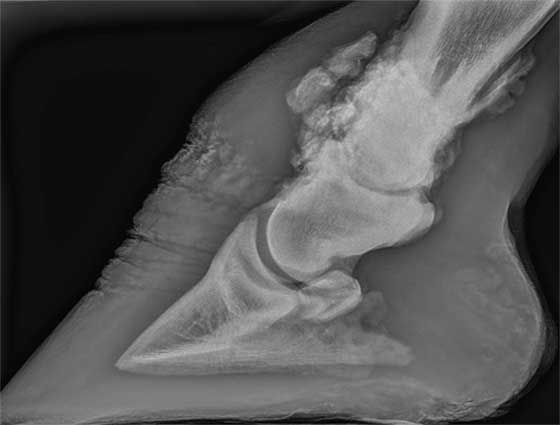

Syndromen naviculaire, éparvin, orseoarthrose, déformations,… nous avons enfin une solution pour ce genre de problèmes: Backsound®.

Backsound est un traitement à base d’injections locales qui suscitent une réaction immunitaire du cheval à l’endroit exact d’où émane la douleur. Durant son administration, nous utilisons un appareil qui détermine le site de traitement avec une précision de 0,5mm: un vrai travail au millimètre.

Nous avons développé Backsound® pour les chevaux souffrant de douleurs chroniques aux pieds et aux membres et pour lesquels aucun traitement ne se montre efficace. Une liste non-exhaustive d’affections peuvent être traitées avec cette technologie:

- Syndromen naviculaire

- Eparvin

- Osteoarthrose

- Calcifications

- Inflammations articulaires

- Fractures de la phalange distale

- Suros

- Résorption osseuse

- Déformations

- Lésions cartilagineuses

- Daarom is een degelijke diagnose met RX, echografie en/of MRI-scan van de patiënt van groot belang om goede resultaten te bekomen en risico's van vb. peesblessures te vermijden.

- De beste indicatie voor een BackSound® behandeling zijn chronische niet-responsieve vormen van artrose van het hoefgewricht, kroongewricht, kogelgewricht, carpus (voorknie) en spronggewricht (spat).